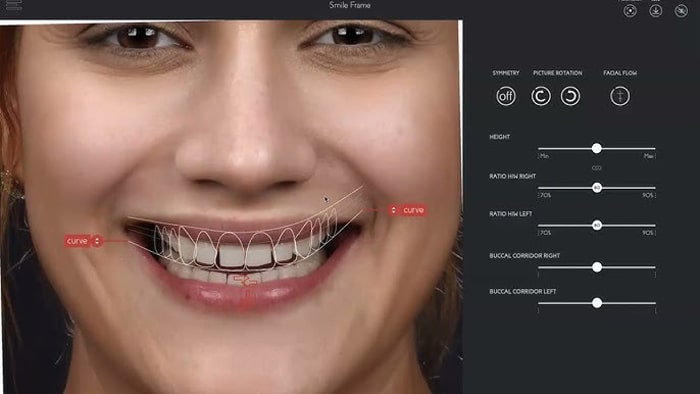

برای رسیدن به یک لبخند زیبا، بدون اینکه به سلامت دندان ها آسیبی برسد، باید به یک دندانپزشک ترمیمی و زیبایی ماهر و باتجربه مراجعه کرد؛ پزشک متخصص، وضعیت دهان و دندان هایتان را بررسی می کند و بهترین روش درمانی را پیشنهاد می دهد. برای مشخص کردن بهترین روش درمان، فرم صورت، رنگ پوست، مو، چشم و …، تناسب عوامل صورت و لبخند، فرم دندان ها، فرم لب ها، تناسب طول و عرض دندان ها، قوس دندانی و عوامل بسیار دیگری باید به دقت بررسی شوند.

بر اساس شکل، اندازه، رنگ دندان و تناسب آن ها با چهره شخص، دندان پزشک متخصص، طرح لبخند متفاوتی را مشخص می کند.